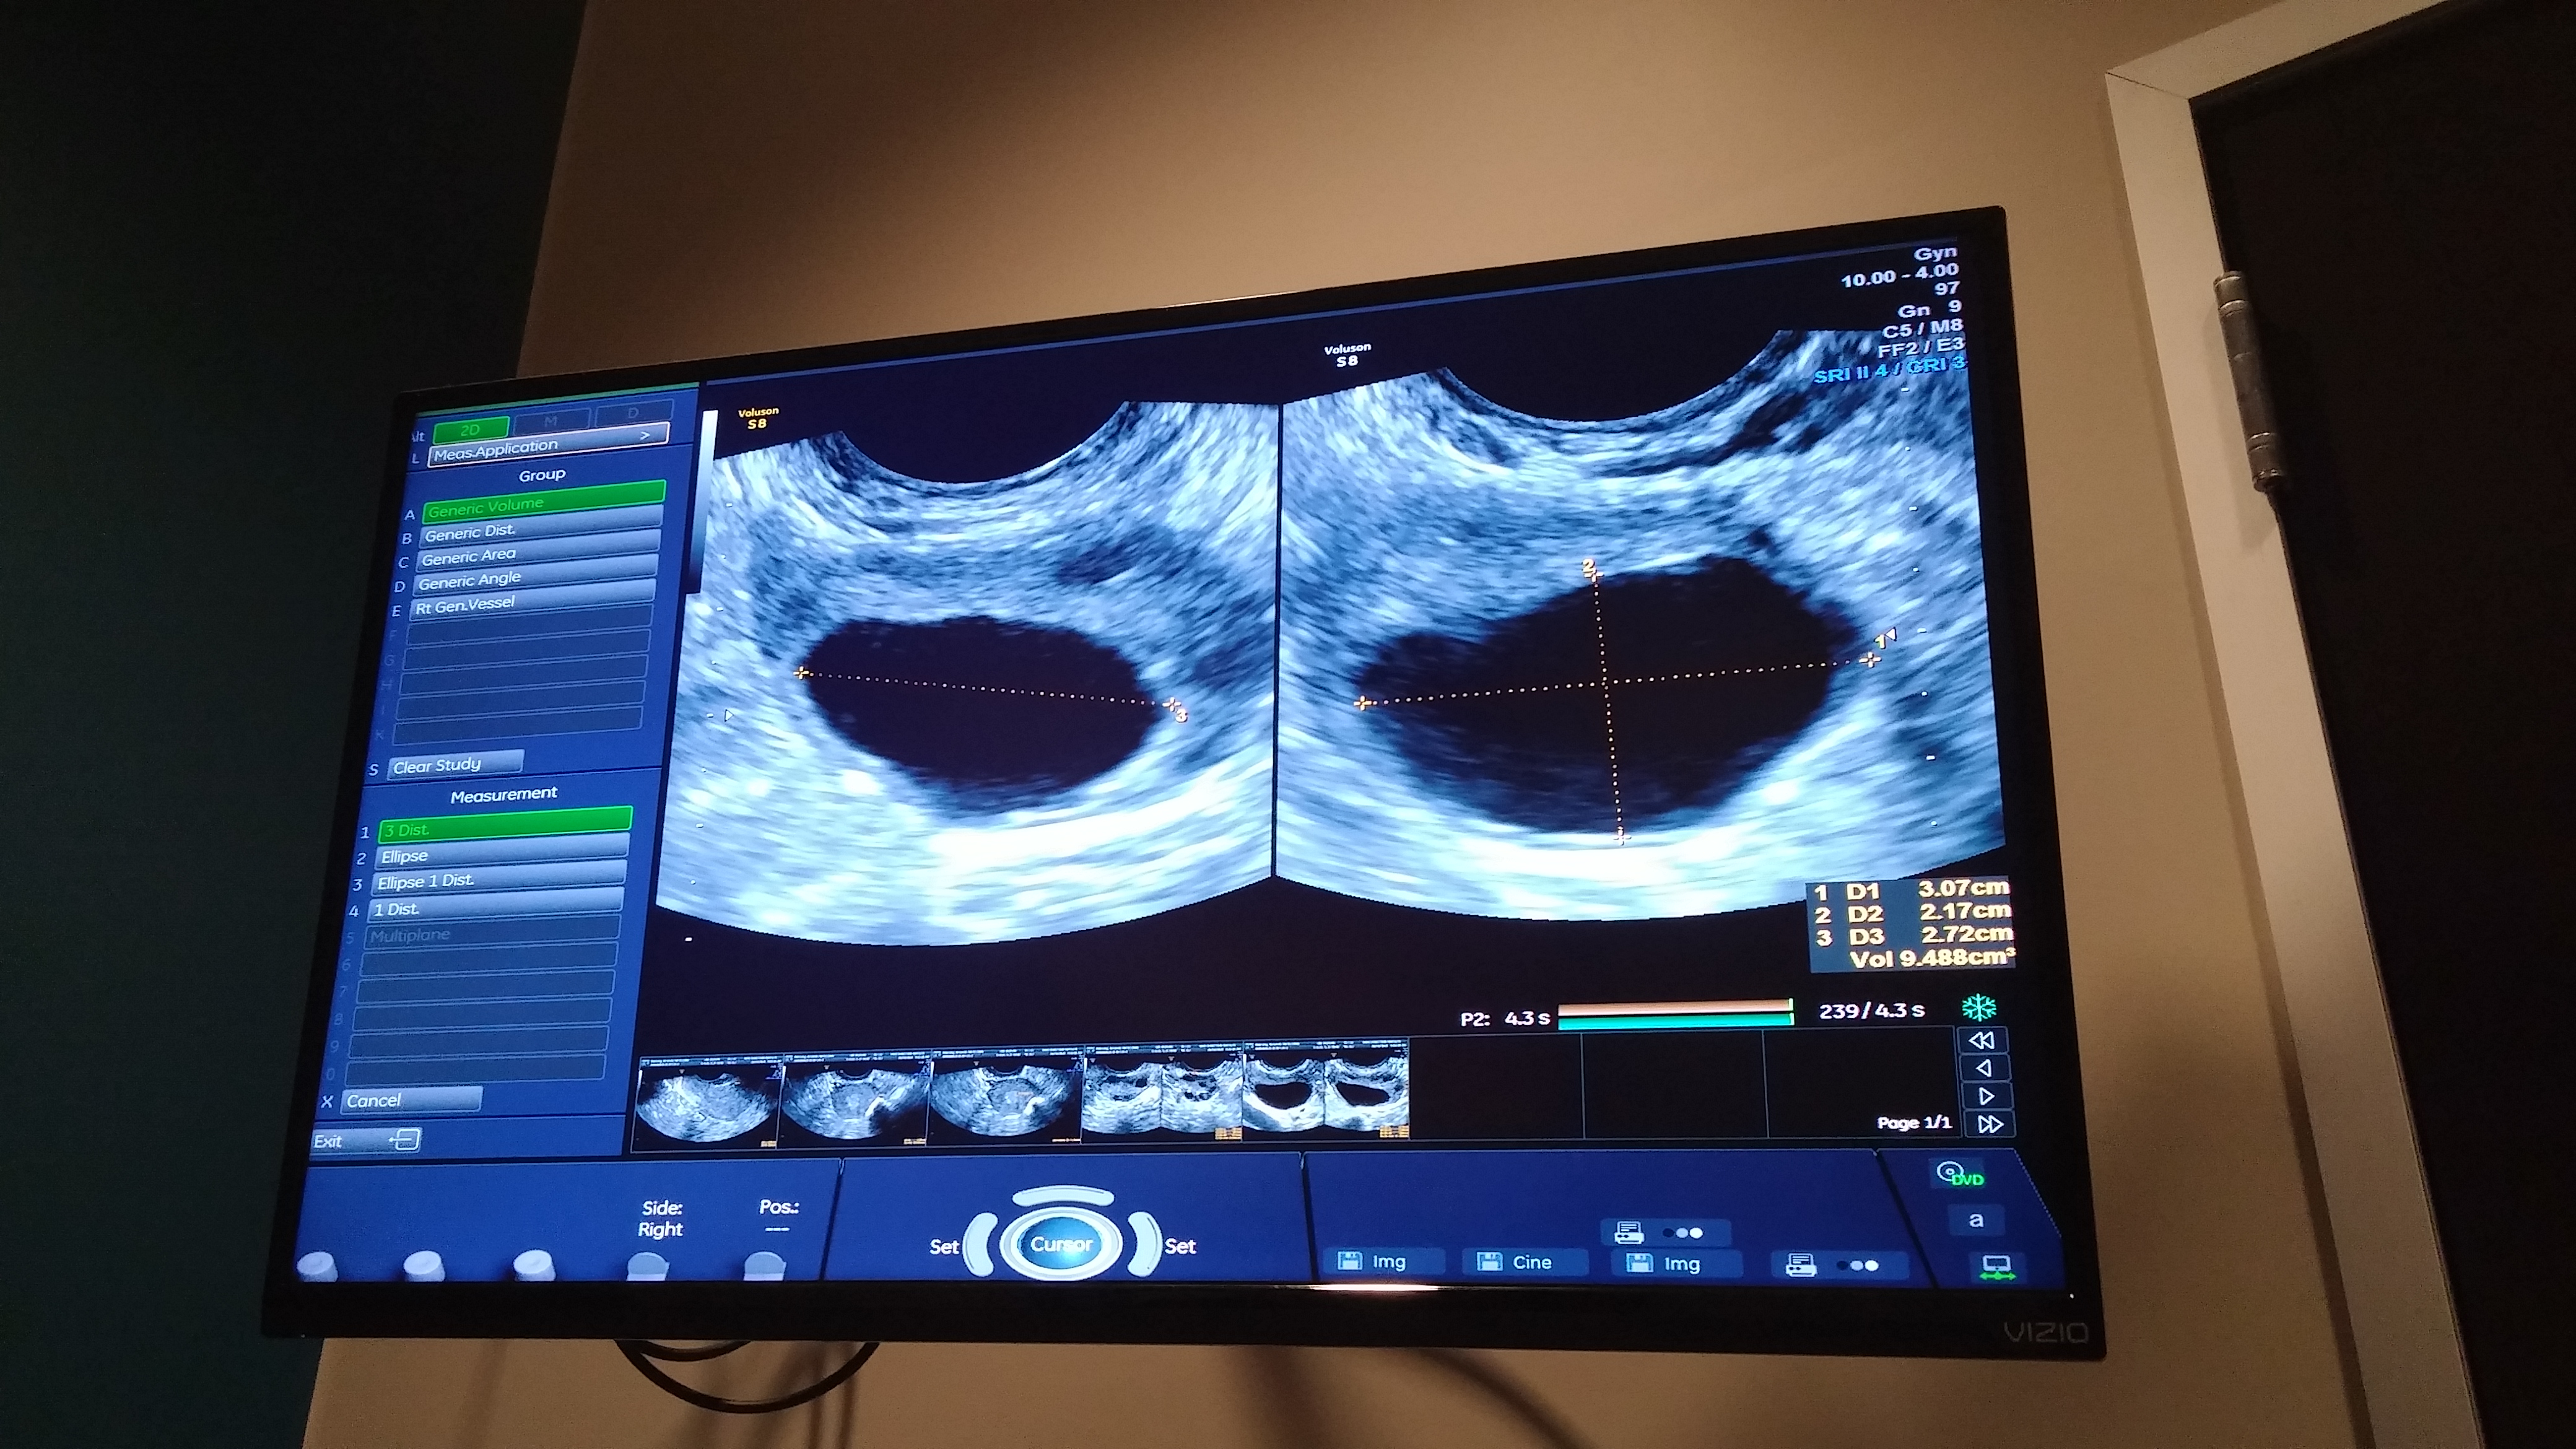

So we had our 3 week follow up ultrasound to check on the progress of the cyst and see if it has gone away yet. Thankfully, it seems that the birth control has done it’s job and deflated the cyst in the ovary! The cyst now measures much smaller and looks kind of like a flattened blob. I also have fewer un-developed eggs in both ovaries which I think is also a positive sign as the mature eggs will be easier to see and count once we have started treatment. Dr. Amols said that I should finish the pack of birth control (which will be today) and then call them when I get my period again so we can do another baseline ultrasound before putting me on the fertility medication.